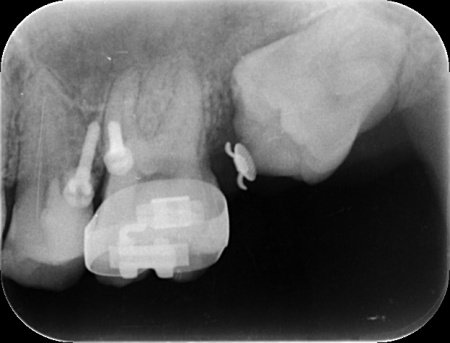

拝見したところ、左上奥歯(第2大臼歯)には被せ物が装着されていましたが、その下で虫歯が再発しており、歯の温存が難しい状態でした。

抜歯後の治療方法には、顎の骨に人工歯根を埋め込むインプラントなどがありますが、患者様の年齢が若いことを考慮して、抜歯部位の後ろに埋まっている親知らずを利用する方法を検討しました。

続いて歯茎に矯正用インプラントと呼ばれるネジを打ち込み、これと隣の歯を固定源としながら、埋まっている親知らずを矯正の力で引っ張りだしました。

矯正治療により、親知らずが歯並びのラインに収まってきたところで、歯根の先端を手前側に起こす力を与えるためにワイヤーをかけ、歯を移動させながら歯列が平行になるように調整します。